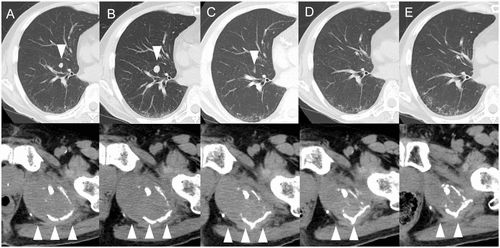

这是一位肝癌出现肺转移患者在接受阿替利珠单抗联合贝伐珠单抗治疗后的肺部转移瘤的CT断层扫描图,其中图A到E箭头所指示的就是用药第1-5个疗程肺部转移瘤的大小。

可以发现,在第二个疗程,也就是图B,明显发现转移瘤体积增加,而到了第3、4、5疗程,转移瘤体积又出现了明显缩小,最后完全消失[1]。